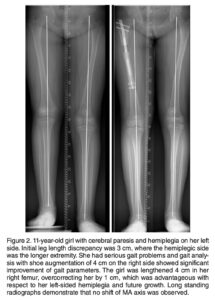

Sob a coordenação do Dr. Marcelo Pigatto D’Amado, membro da Sociedade Brasileira de Ortopedia e Traumatologia e da AO Foundation, o CBOT é pioneiro no uso de hastes intramedulares motorizadas (PRECICE, FITBONE) para alongamento ósseo no Brasil.